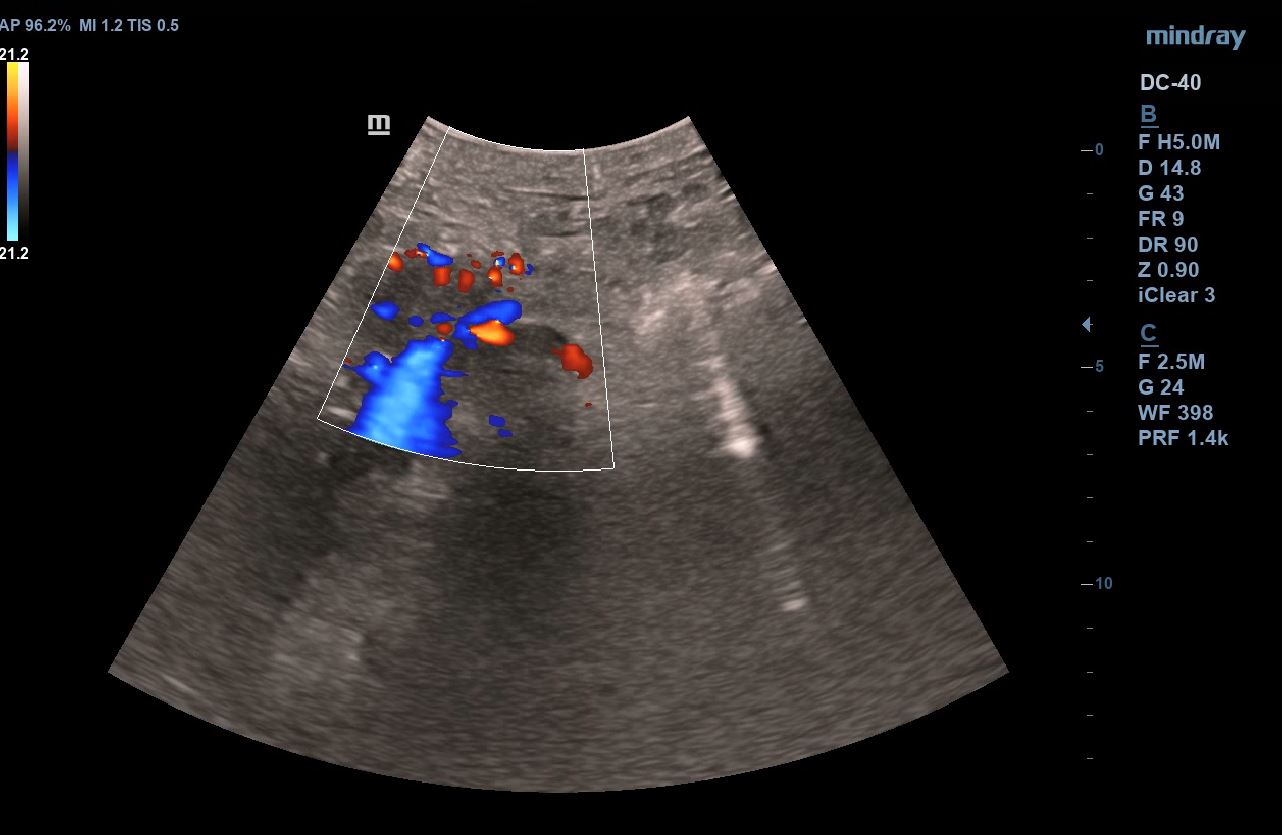

Se realiza ecografía clínica abdominal visualizando en región epigástrica masa de 5,7 x 4,6 cm de aspecto heterogéneo, con un componente principal hipoecogénico y áreas de mayor intensidad. Presenta mapa color positivo y dilatación de colédoco.

Se inicia estudio, confirmando en ecografía abdominal reglada la presencia de una masa sólida en cabeza-cuello pancreático de 5 x 4 cm con dilatación de la vía biliar intra y extrahepática y en TAC toraco-abdomino-pélvico masa hipervascular en cabeza y cuerpo pancreático con áreas de degeneración quística, dilatación del árbol biliar y atrofia del páncreas distal. Posteriormente, se realiza una ecoendoscopia en la que se informa de una masa pancreática con engrosamiento de la papila duodenal, así como dilatación de la vía biliar extrahepática.